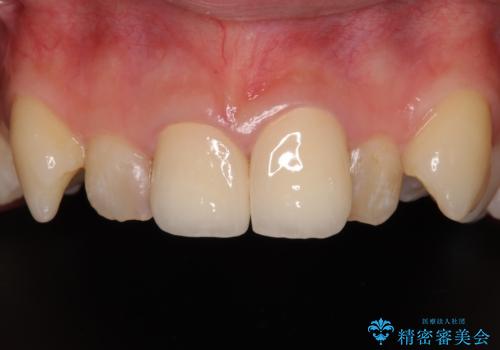

[ セラミック治療 ] 前歯の変色をきれいにしたい

担当医 大元洋佑

![[ セラミック治療 ] 前歯の変色をきれいにしたいの症例 治療前](https://seimitsushinbi.jp/wp/wp-content/uploads/2023/12/8095b301c8ea19cbf7179d372450bebf-500x350.jpg?v=1703129532)

![[ セラミック治療 ] 前歯の変色をきれいにしたいの症例 治療後](https://seimitsushinbi.jp/wp/wp-content/uploads/2023/12/528aed1286d6fd20e773cd5dfb0c7971-500x350.jpg?v=1703129602)